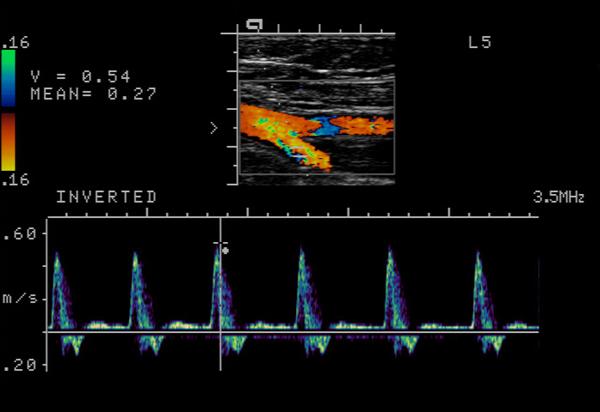

Explain the waveform of the ICA

low resistant - constant forward flow

Forward flow throughout the cardiac cycle